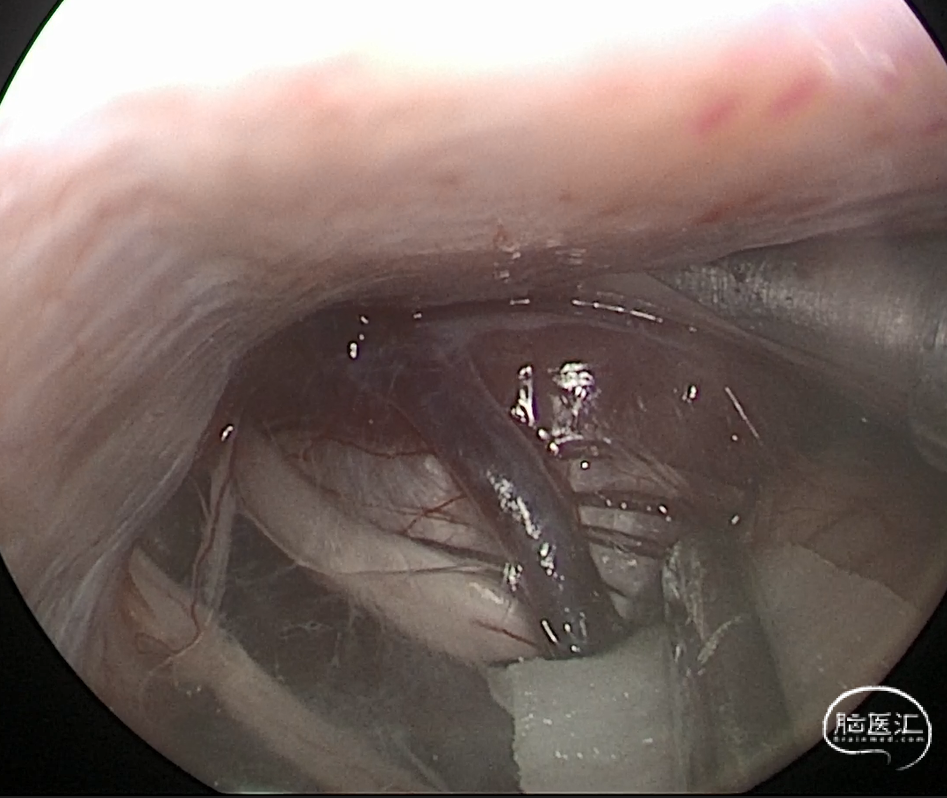

术中图片

针对本病例,幕下小脑上入路有以下优势:

1. 是一种简单、安全、有效的手术方法,可以充分暴露蝶岩斜区的肿瘤和重要结构,如脑干、小脑、颅神经、基底动脉等;

2. 可以避免或减少对颞叶、颞下回、颞极、颞下静脉和颞下动脉的牵拉和损伤,从而降低术后的神经功能障碍和并发症;

3. 可以在不切开小脑幕的情况下,通过小脑幕切迹和小脑桥脑前外侧间隙,直接到达肿瘤的上限和内侧界,从而提高肿瘤的切除率和根治率;

4. 可以结合内镜技术,利用内镜的放大、照明和视角优势,进一步扩大手术视野,提高肿瘤的显露和切除,同时减少对周围正常组织的损伤。